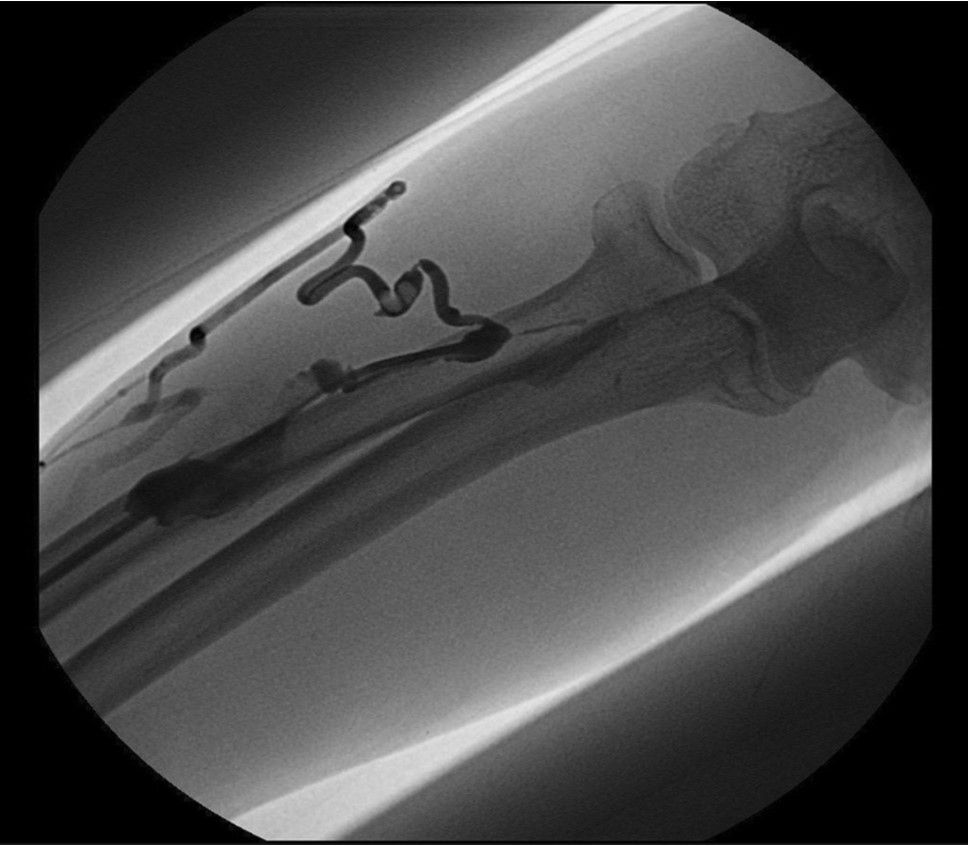

Initial shuntogram 상 total stenotic occlusion된 antecubital vein과 cephalic & basilic veins이 확인되었다(Fig. 1) 투시하에서 더 이상의 outflow vein을 확인할 수 없었으며 초음파상 1mm 크기에 가까운 흔적으로 확인되었다(Fig. 2). 7Fr, 24cm sheath(Accu-Sheath, Sung wonmedical, Korea, Cheongju) 로 폐색된 앞부위까지 전진시킨 후, 투시를 보조수단으로 하며 초음파를 main 유도 기구로 사용하여 real time으로 초음파 probe를 0.035’ J-tip & straight-tip guide wires(Terumo, Tokyo, Japan)와 5 Fr Kumpe catheter(Soft-Vu, AngioDynamics, USA, NY) 바로 위에 위치 시키면서 wire를 전진시켰다(Fig. 3). 시술 중 guide wire 가 혈관 외부로 뚫고 나가며 parenchymal injury를 유발하였다(Fig. 4A, B). 그 후 venous true lumen을 찾 angioplasty를 시행하였다(Fig. 5). 마지막 shuntogram 상 더 이상의 혈관 손상이 없이 재개통된 것을 확인하고 시술을 종료하였다(Fig. 6).

Fig. 3.

Guide wire negotiation to occluded antecubital vein under only US guide Korean